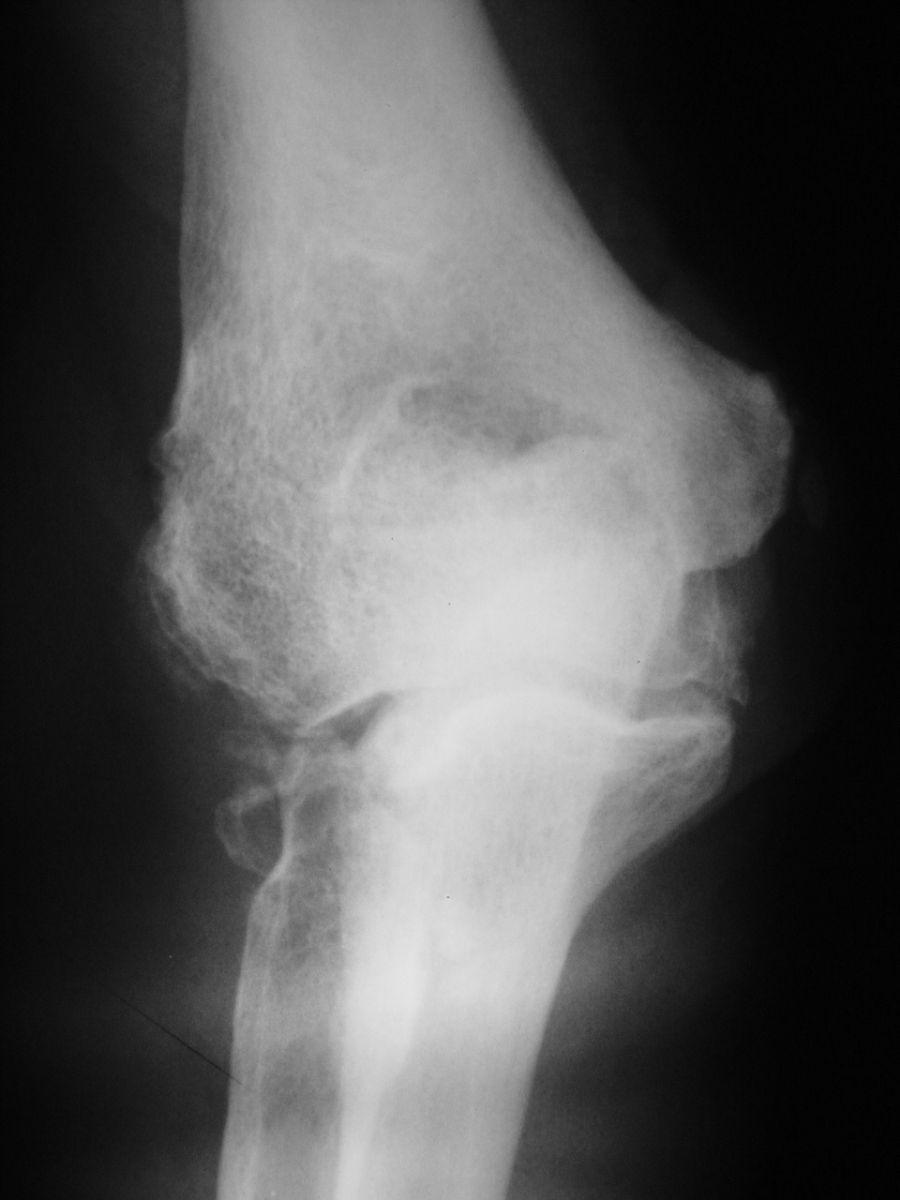

| Case 1. This 80 year old man developed wrist and elbow pain years after radial head excision for fracture. Radiographs show proximal migration of the radius resulting in valgus instability of the elbow, radiocapitellar impingement and distal ulnar impaction. This pattern of longitudinal forearm disruption, proximal radial fracture and dislocation of the distal radioulnar joint, is referred to as the Essex-Lopresti fracture dislocation. |